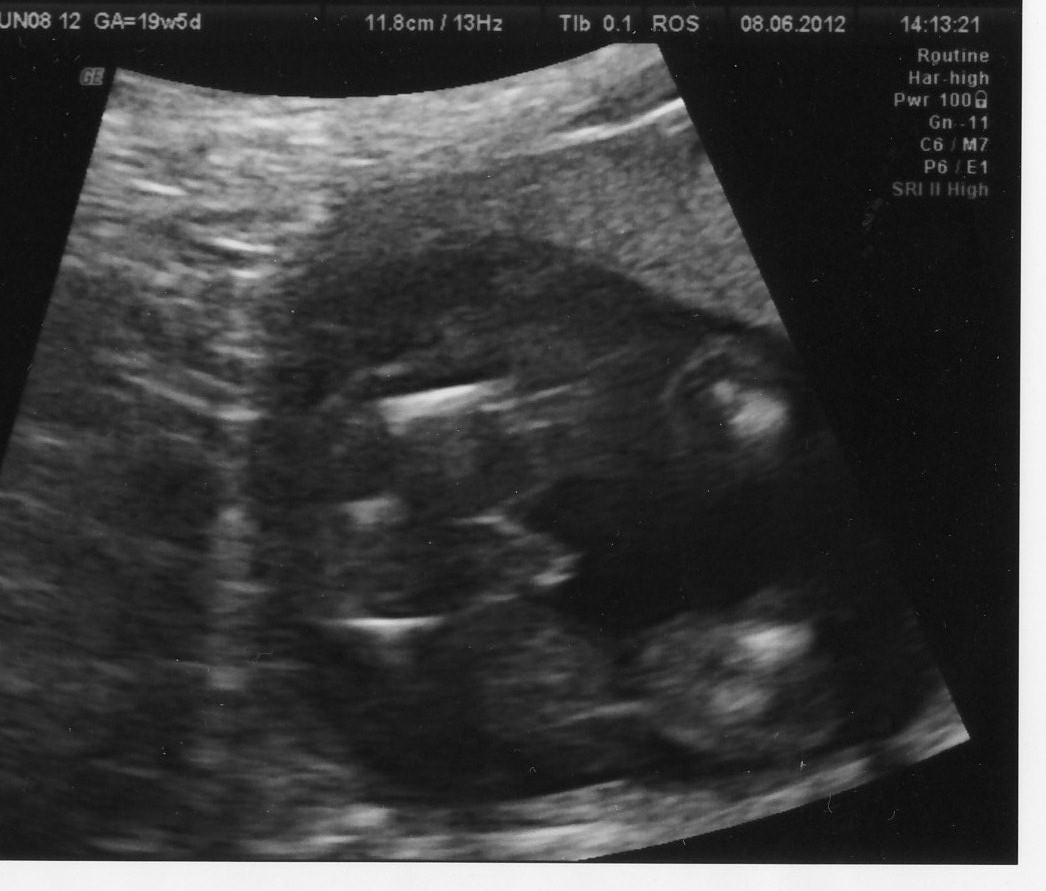

NEW PIC ADDED ON LAST PAGE Hi everyone. Here is a pic from my 20 week scan last week. Tech was pretty sure she was looking at a little boy, our first after 3 daughters!! Of course I have no experience with little boy bits but this has to be a boy right? Appreciate any thoughts. Thanks :)

Attachment 3241